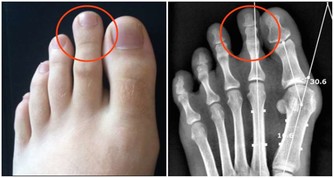

膝關節磨損不可修復

而且,這種對膝蓋的磨損是不可修復的!磨損如果過度嚴重,只能夠置換關節!

一方面我們需要鍛煉大腿和臀部的肌肉群。但是另一方面,我們又不能以傷害膝關節為代價,因為膝關節的壽命由基因決定,是60年,過度使用會加重對它的磨損,並且不可修復。

在堅硬地上所有劇烈運動,比如下蹲、蛙跳、跑步、跳繩還有跳舞,都會加重對膝蓋骨的磨損。尤其是蹲下去再站起來,對關節的磨損最大。關節軟骨大概有1到2毫米,作用就是緩沖壓力,保護骨骼不破裂。

它就相當於跑道上的橡膠,能夠幫助我們緩衝上下運動時的一個力,進而來保護我們的關節。如果非要在堅硬地板上運動,在超強的反作用力下彈回來,對關節和骨骼的損傷相當大。因此,建議只在橡膠運動場地做運動。

在爬山和爬樓梯的時候,膝關節會承受超過本身體重3到4倍的壓力。尤其是50歲以後,人的膝關節多少都會有些磨損的情況,此時,就要減少此類運動。對於有些有過膝關節損傷的朋友40歲以後就要特別注意了。